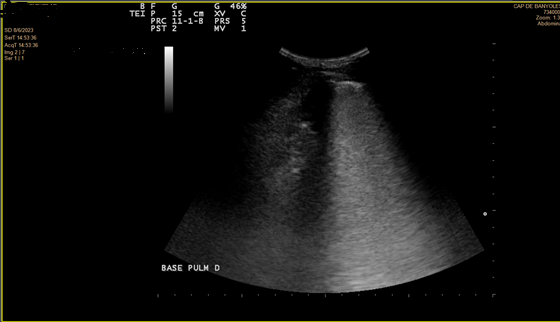

En la ecografía se objetiva irregularidad en la línea pleural, líneas B coalescentes (light beam) y un patrón de consolidación pulmonar en ambas bases pulmonares (I > D).